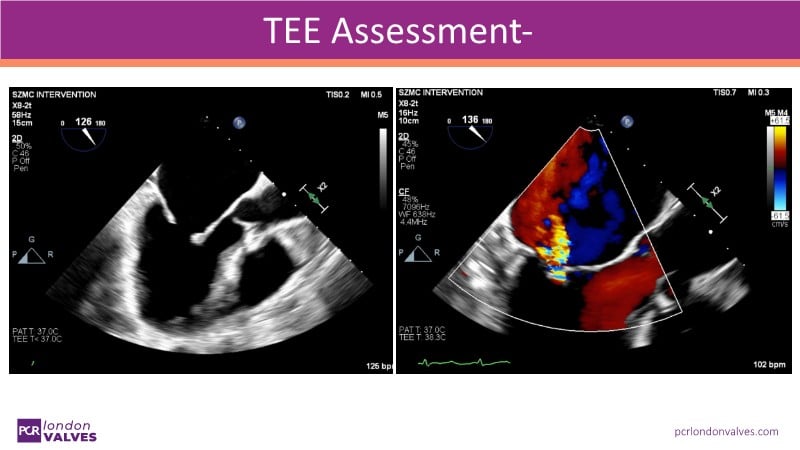

This LIVE case symposium brings mitral regurgitation guidelines into real clinical practice. Through step-by-step patient demonstrations and insightful discussion, the session explores how recommendations guide decision-making in ventricular and atrial secondary MR, how the heart team tailors therapy to individual anatomy and comorbidities, and how device iterations and procedural workflow can influence outcomes.